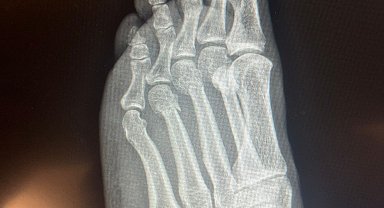

Özgür Özel'den, 'ayağından vuruldu' iddialarına röntgenli yanıt